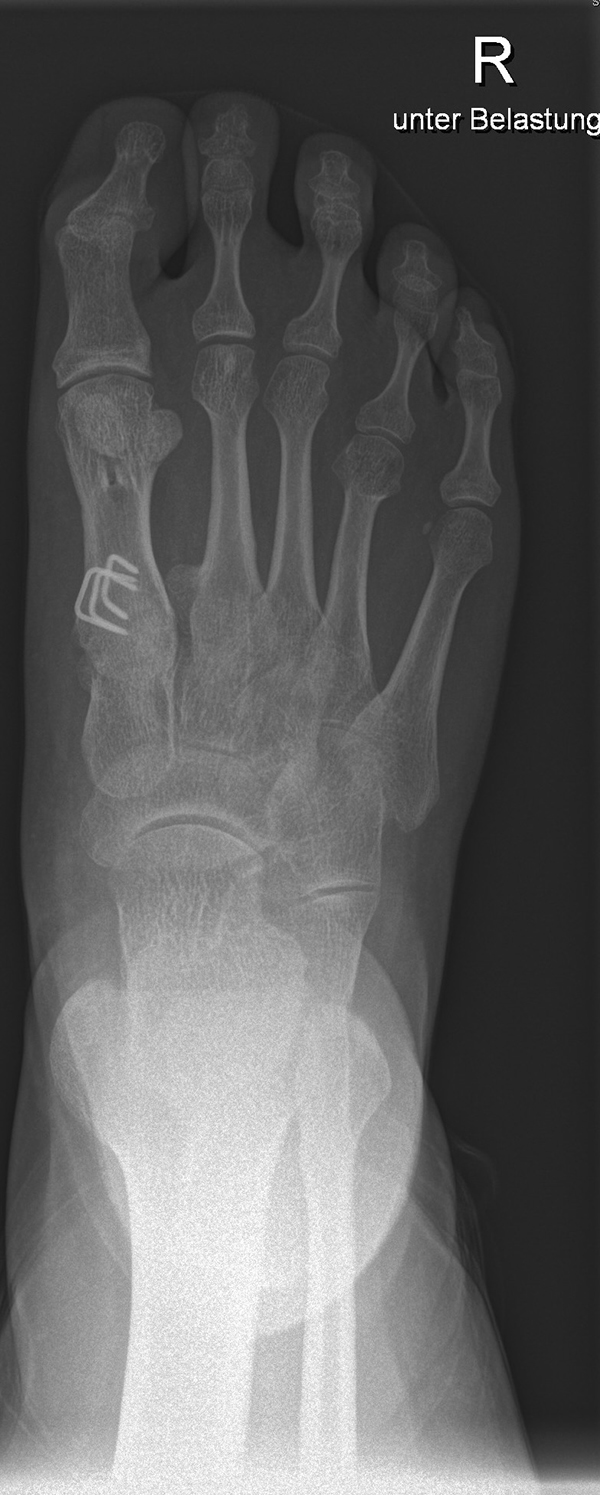

In der Regel bestehen aktive Wachstumsfugen bei Mädchen bis zum 12. und bei Jungen bis zum 14. Lebensjahr, mit Abweichungen von einem Jahr nach unten und nach oben. Präzise Informationen unter anderem darüber gibt das präoperative Röntgenbild (Abb. 2).

Abb. 2 a-c: offene Wachstumsfugen MT I Basis und Zehen (a), teilweise geöffnete Wachstumsfugen (b) und geschlossene Wachstumsfugen (c).